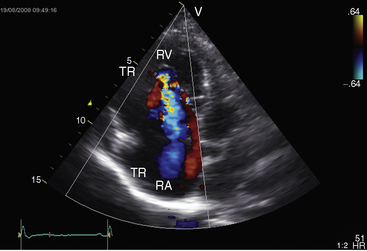

Echocardiography with color flow imaging and Doppler interrogation is the diagnostic test of choice and is used to establish the diagnosis and severity of Ebstein’s anomaly.17,25,89,90 The diagnosis can be made in utero.51,59,60 Apical displacement of the septal tricuspid leaflet in the anomaly exceeds 15 mm in children and 20 mm in adults (Figure 13-30).89 The right atrium proper lies proximal to the anatomic tricuspid annulus, and the atrialized right ventricle occupies the interval between the anatomic tricuspid annulus and the distally displaced septal tricuspid leaflet (see Figure 13-30). The displaced tethered septal tricuspid leaflet moves little if at all in contrast to the large elongated anterior leaflet, which may exhibit brisk sail-like movements in real-time imaging (Figures 13-30 and 13-31). Rarely, a broad echogenic band separates the atrialized right ventricle from the distal functional right ventricle, and the proximal annulus is unguarded by tricuspid leaflet tissue (Figure 13-32).

Echocardiography defines left ventricular geometry and cavity size, and real-time imaging identifies displacement of the ventricular septum into the left ventricular cavity with paradoxical septal motion (see Figure 13-31).29 Superior systolic displacement (mitral prolapse) occurs because normal-sized leaflets and chordae tendinae are housed in a left ventricular cavity that is reduced in size and altered in shape (see Figure 13-31).29 The right ventricular outflow tract in the short axis is dilated in contrast to the adjacent normal or small aortic root. Color flow imaging and Doppler interrogation quantify tricuspid regurgitation and establish the relatively low velocity of regurgitant flow, which begins at the level of the displaced septal and posterior leaflets and courses through the atrialized right ventricle into the right atrium proper (Figure 13-33, Video 13-1, and Figure 13-34).